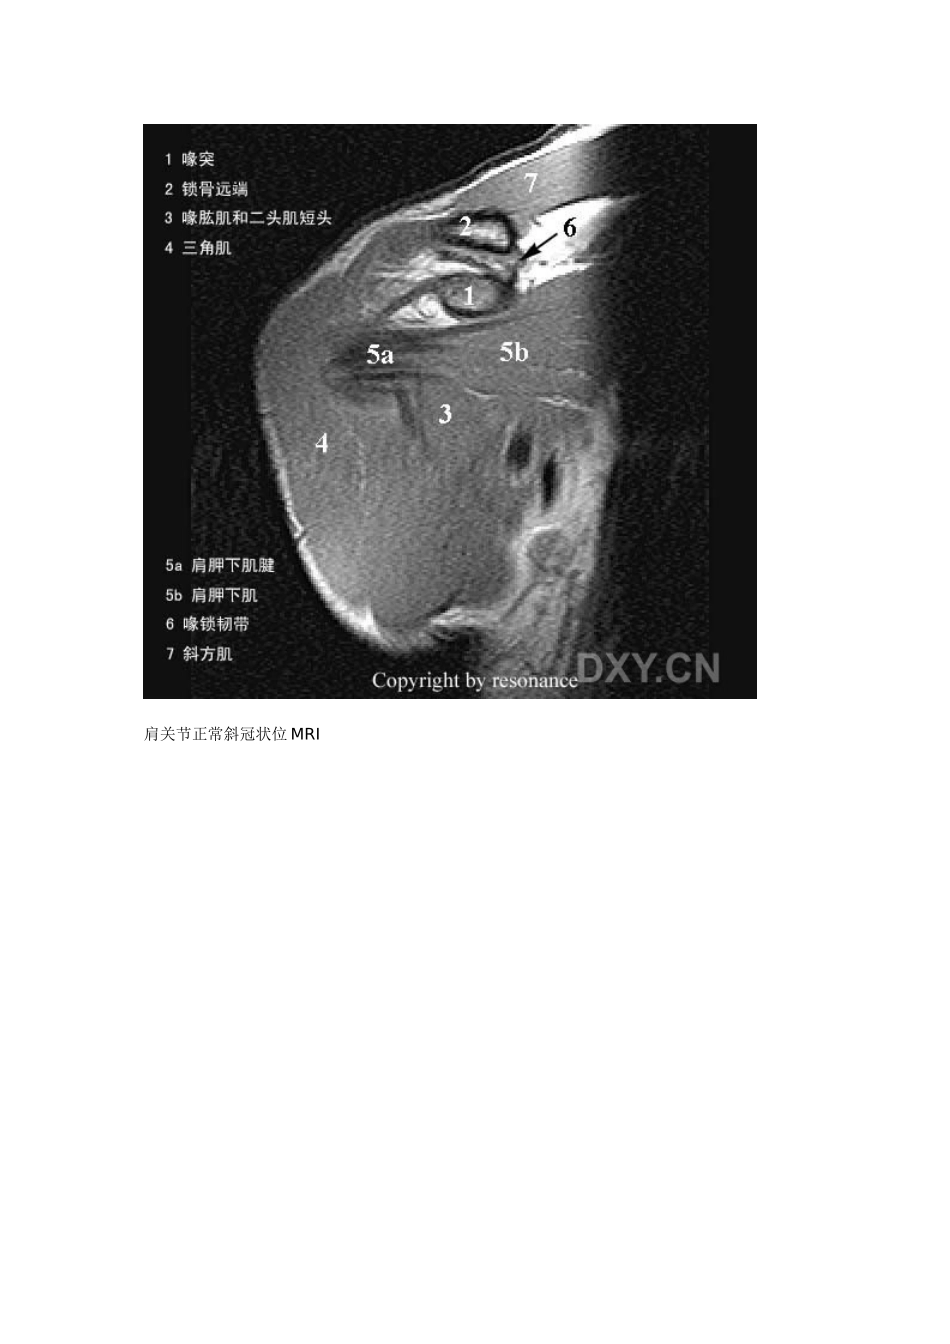

肩关节正常斜冠状位 MRI肩关节正常斜冠状位 MRI肩关节正常斜冠状位 MRI肩关节正常斜冠状位 MRI肩关节正常斜冠状位 MRI肩关节正常斜冠状位 MRI肩关节正常斜冠状位 MRI肩关节正常斜冠状位 MRI肩关节正常斜冠状位 MRI肩关节正常斜冠状位 MRI肩关节正常斜冠状位 MRI肩关节正常斜冠状位 MRI肩关节正常斜矢状位 MRI肩关节正常斜矢状位 MRI肩关节正常斜矢状位 MRI肩关节正常斜矢状位 MRI肩关节正常斜矢状位 MRI肩关节正常斜矢状位 MRI肩关节正常斜矢状位 MRI肩关节正常斜矢状位 MRI肩关节正常斜矢状位 MRI肩关节正常斜矢状位 MRI肩关节正常横断位 MRI肩关节正常横断位 MRI肩关节正常横断位 MRI肩关节正常横断位 MRI肩关节正常横断位 MRI肩关节正常横断位 MRI肩关节正常横断位 MRI肩关节正常横断位 MRI肩关节正常横断位 MRI肩关节正常横断位 MRI肩关节正常横断位 MRI肩关节正常横断位 MRI